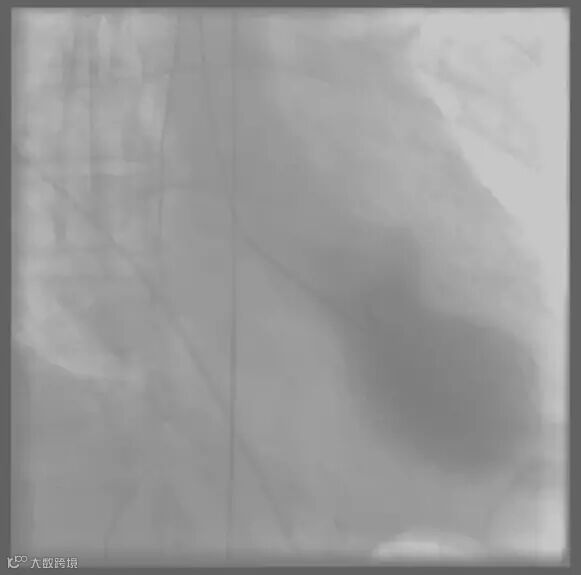

TCM最先在日本被报道,由于本病发作时,心尖呈气球样,形状颇似传统日本渔民为捕获章鱼而设置的章鱼壶。

图片来自Wikipedia

造影图片中,我们可以清晰地看到TCM患者紧缩的心脏如同章鱼壶一般。